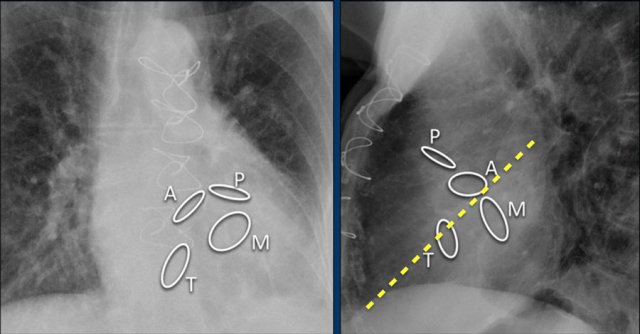

Here we see the normal valve position on an PA and lateral chest X-ray.

On the lateral chest film the aortic and pulmonary valves are located above the line from base of the heart to the apex and tricuspid and mitral valves are below this line.